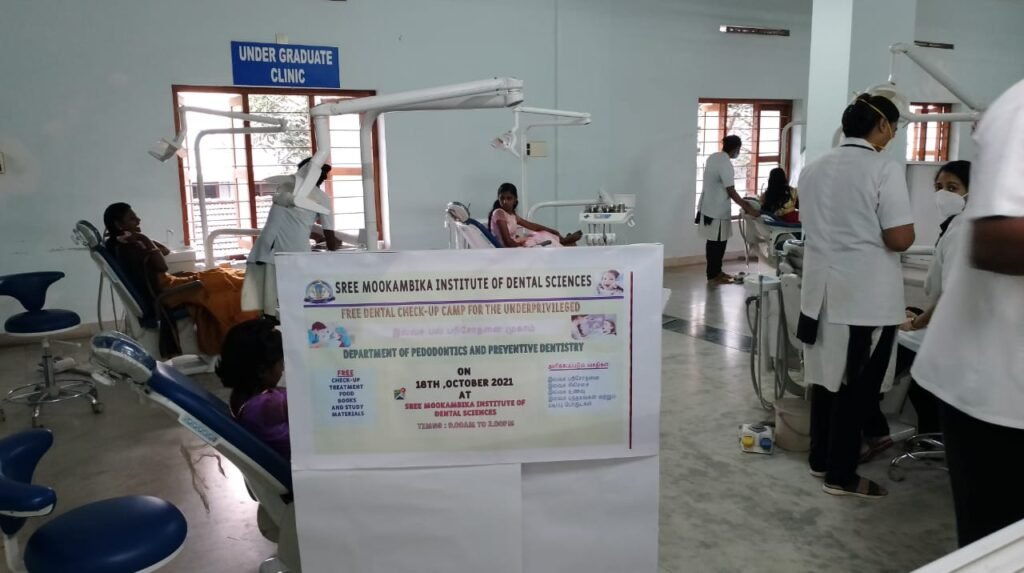

6.WORKSHOPS, CDE’S, CAMPS AND SEMINARS

School Dental Camps